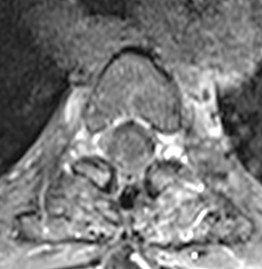

Pacientă în vârstă de 54 ani, cu un istoric îndelungat de neoplasm mamar, care acuză scăderea forței musculare în membrul inferior drept. RMN de coloană toracală a evidențiat o tumoră intramedulară T3-T4 de cca. 20/9/8 mm, centrală, relativ bine delimitată, care captează substanța de contrast – aspect sugestiv pentru o determinare secundară (metastază).

Intervenția chirurgicală s-a desfășurat respectând principiile și tehnicile microchirugicale, sub anestezie generală și monitorizare electrofiziologică intraoperatorie pentru a reduce la minim riscul de agravare neurologică. Nu putem sublinia îndeajuns importanța acestor două aspecte: tehnica microchirurgicală și monitorizarea electrofiziologică, având în vedere miza deosebită a acestei operații. Măduva toracală prezintă o densitate extraordinară de fibre nervoase, fiecare milimetru de țesut medular rezecat putând însemna o funcție neurologică afectată definitiv. De aceea, este necesar ca în timpul intervenției să se îndepărteze numai țesutul tumoral, nu și cel nervos. Pentru aceasta, microscopul operator și continua monitorizare a funcțiilor neurologice sunt esențiale și fără ele nu se poate imagina o asemenea operație.